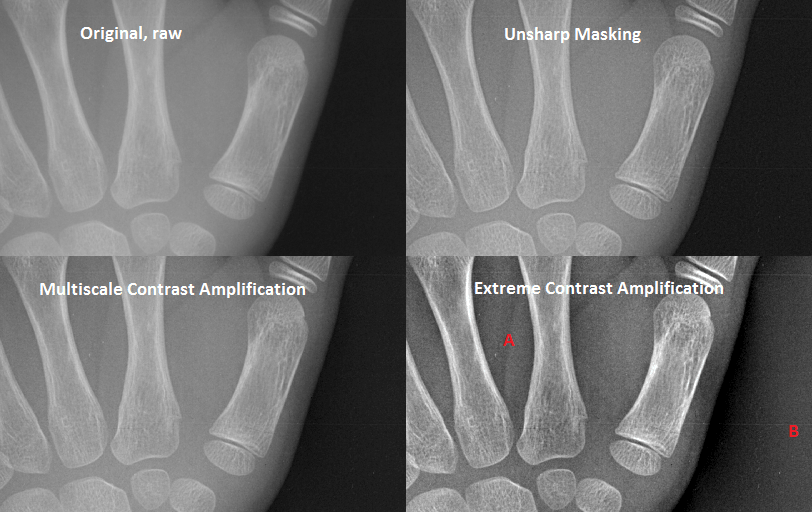

The radiographs produced in modern digital radiology departments have often use “image post-processing” by software associated with the modality itself. The main purpose is rendering the details more visible for the human eye. Twenty years ago, the method of choice was unsharp masking. It enhances edges at a certain scale (i.e. distance) e.g. 0.4 mm. However, this is useful only when used moderately; otherwise it leaves clearly visible dark “halos” around white objects. The figure below illustrates this, showing a raw image and a version with unsharp masking.

In 1994 Agfa invented multiscale image contrast amplification (Musica). It enhances edges at several scales at once, so that the halo effect spreads and does not bother the human eye. In addition, it reduces edges at very large scales, which is the same as reducing contrast variations over large distances. This in turn allows scaling up the image grey levels to improve contrast.

The figure above also shows an example of multiscale contrast amplification. Compared to unsharp masking it gives a more pleasant image – it avoids focusing on one spatial frequency and instead gives room for details at many scales. The last example in the figure shows extreme use of contrast amplification. The “long distance” contrast differences almost disappear completely: the grey level inside the hand (at A) are now much darker, while it is much lighter in the background (at B). Such a strong amplification seems unnecessary for hand radiographs. It may be useful in e.g. thorax images.